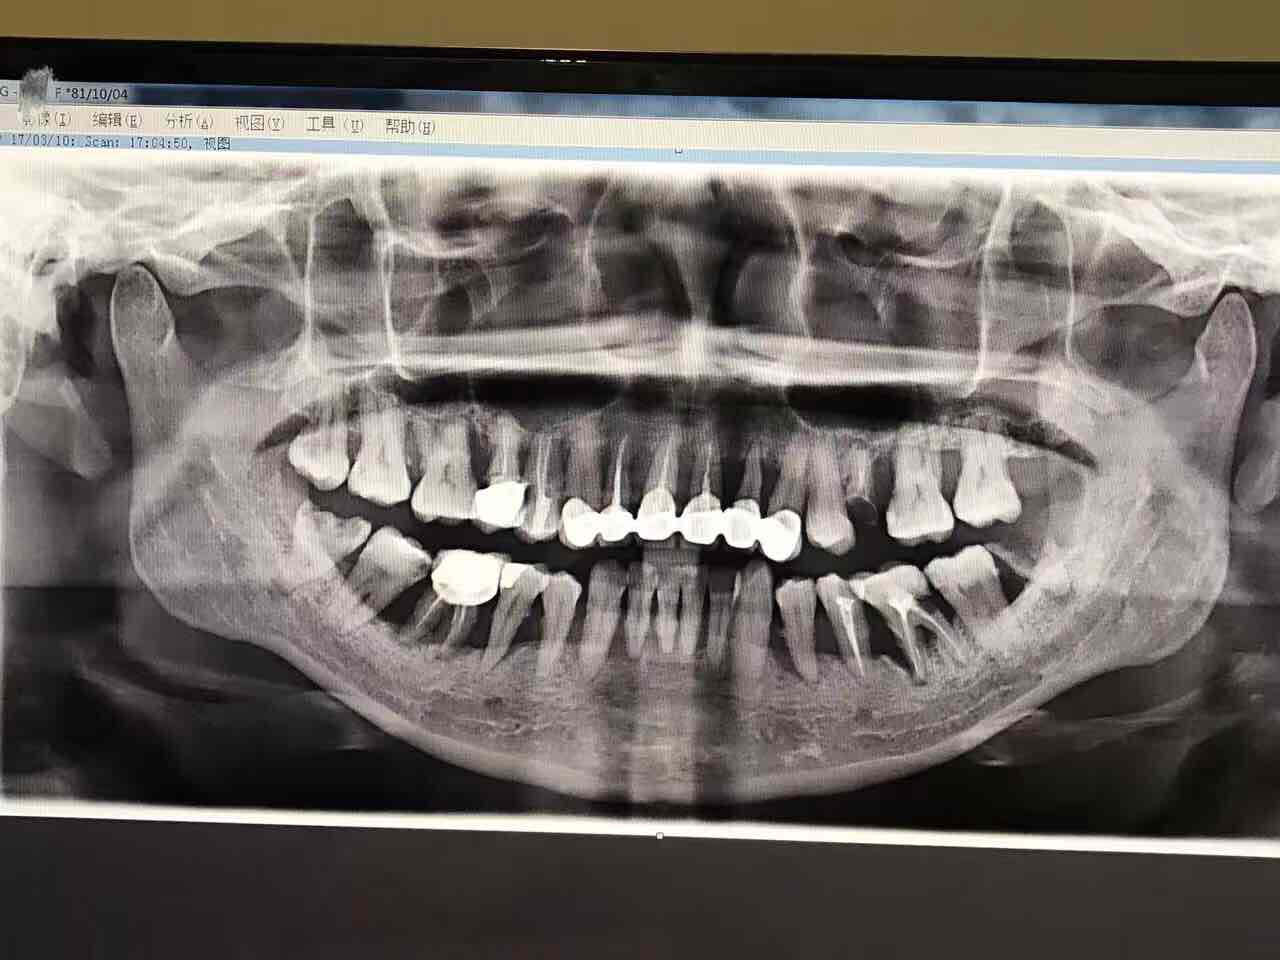

#早交班#讨论的一个病例,81年女性,重度侵袭性牙周炎,主诉要求洗牙,之前在公家医院做过很多治疗,但是从来不知道自己有牙周炎需要治疗,现在来了拍片检查以后发现很多牙齿已经没法挽救了,现在面临着治疗预后差和费用贵的情况........所以说应该要有自己的家庭牙医,有问题上医院往往头痛医头、脚疼医脚,今天A医生看明天B医生看,容易忽视掉症状不明显的慢性疾病,延误治疗[撇嘴]